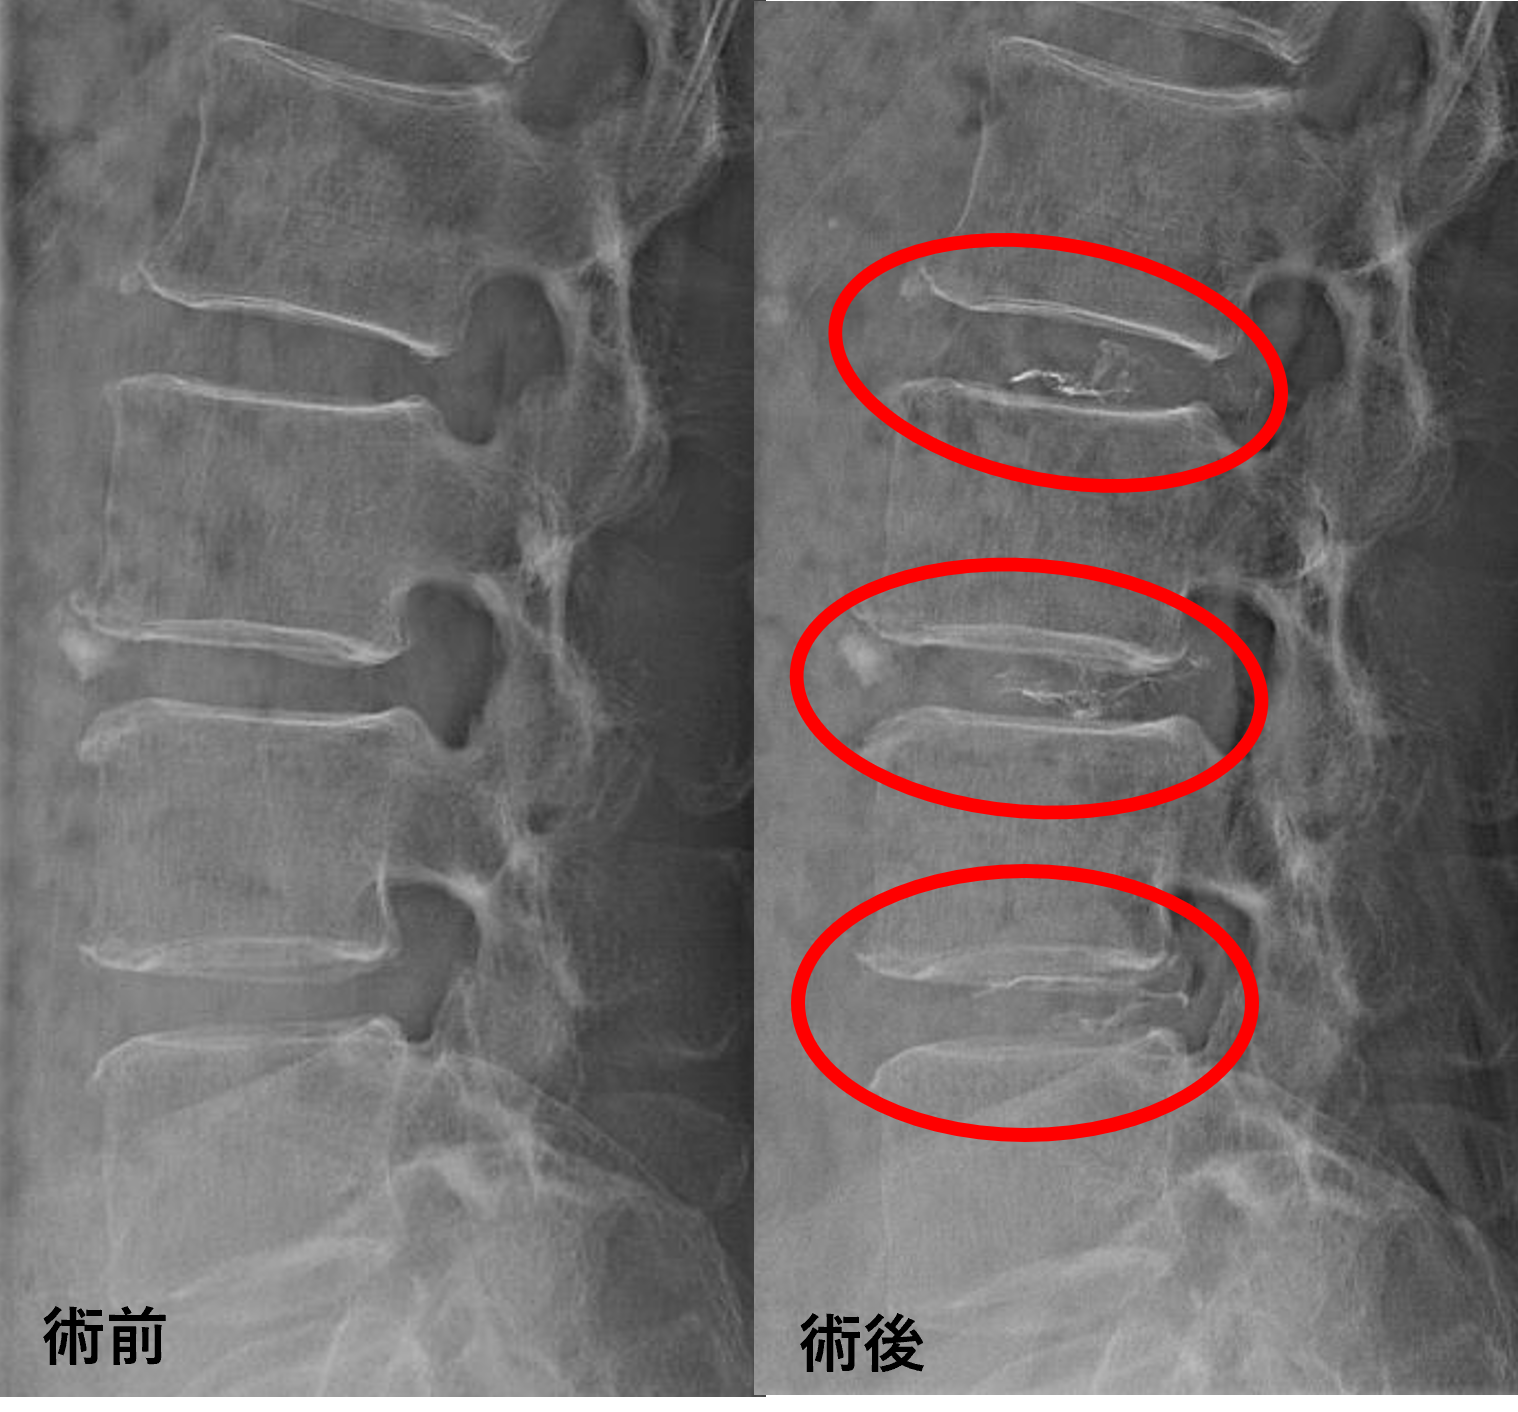

画像及び所見について

- L2/3、3/4、4/5 – 椎間板変性、椎間板ヘルニア、繊維輪断裂

以上のことが画像上認められました。

L2/3、3/4、4/5の椎間板所見による脊柱管の圧排が、症状の原因の可能性が高い。

患者様と相談の元、L2/3、3/4、4/5にセルゲル法を施行